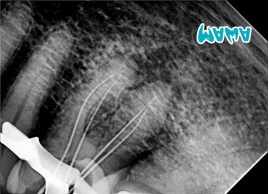

2️⃣ Instrumentación Biomecánica

Se utilizó el sistema de limas ROGIN INO-SHAPER en rotación continua.

La preparación se realizó progresivamente hasta alcanzar una lima 35.04, logrando una conformación adecuada del conducto respetando su anatomía original. Las limas INO-SHAPER ofrecieron una excelente flexibilidad y eficiencia de corte, permitiendo una instrumentación segura y predecible incluso en un caso con anatomía compleja.